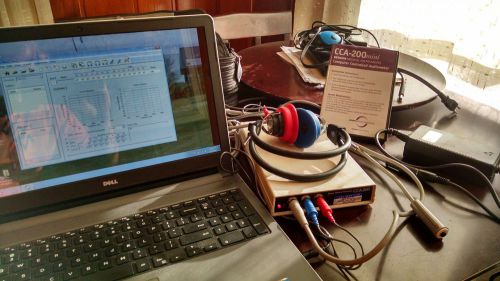

MAICO PILOT AUDIOMETER @ (121224)

Benson Medical Instruments CCA-200 mini Micro-Audiometer